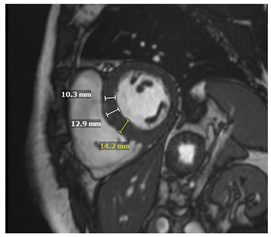

| CMR Parameter | Key CMR Findings | Illustrative Example |

|---|---|---|

| Cardiac Structure and Function |

| ![]() |